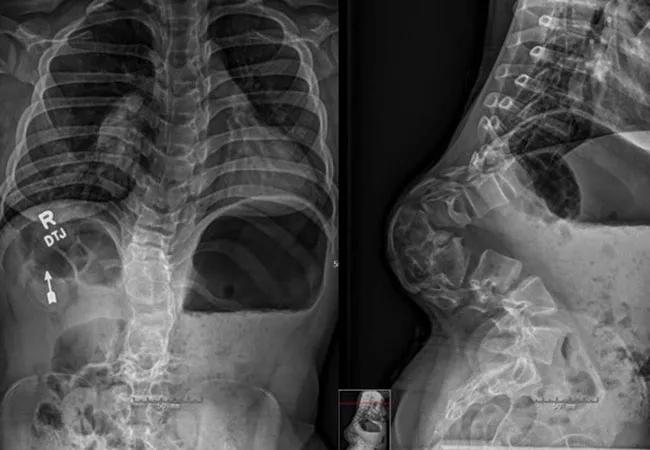

In our patient, full-length antero-posterior and lateral radiographs of the spine revealed an astonishing 150-degree kyphosis. Kyphosis greater than 50-degrees can warrant surgery, even in the absence of neurological symptoms, due to the risk of progression. We found it remarkable that this patient’s neurological function remained intact despite her extreme deformity.

Radiographs and outside MRI also confirmed significant deformity of the thoracolumbar spine as well as tethering of the cord over the apex of the deformity. Considering the patient’s extreme deformity and the likelihood of progression, our only option was a very aggressive surgical approach.

Figure 1. PA scoliosis radiograph of full spine showing mild scoliotic deformity Figure 2. Focused radiograph the the kyphotic deformity. This portion of the spine is typically straight or lordotic.

Figures 4 and 5. Postoperative PA and lateral radiographs of the spine after double pedicle subtraction osteotomy (PSO) at levels T12 and L1 with correction of alignment